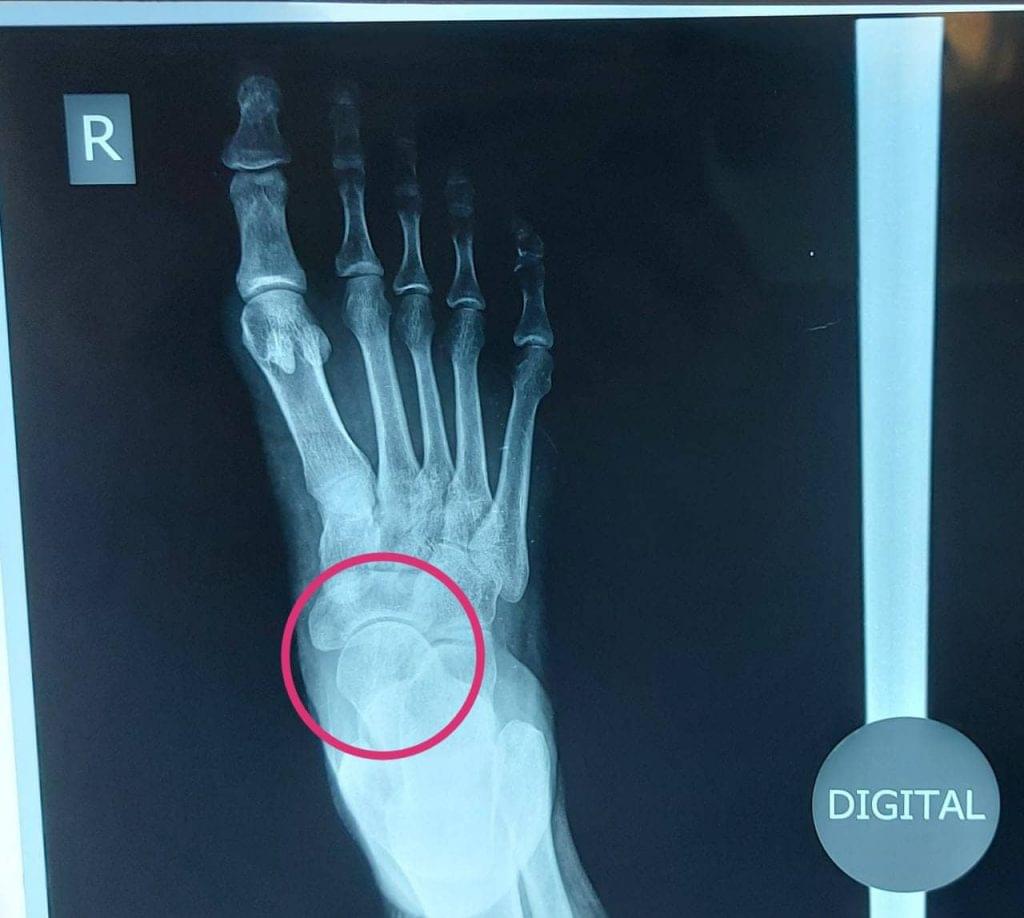

Talonavicular joint pain treatment: Talonavicular joint is part of a 3 joint complex in the foot which all work together for smooth mobilization of the foot and walking. Damage to one joint or bone can affect other joints and disturb walking and create chronic pain and swelling.

Diseases of the Talonavicular joint can be due to injury such as fall, accident, twisting of the foot which cause fracture of the navicular bone and if not treated in time, lead to chronic pain and arthritis.

Another common problem is wear and tear in the bones leading to Arthritis of the Talonavicular joint. Other rare conditions such as avascular necrosis of Talus or Navicular bone, stress fracture, tumor, and unknown infections can also affect this joint complex.